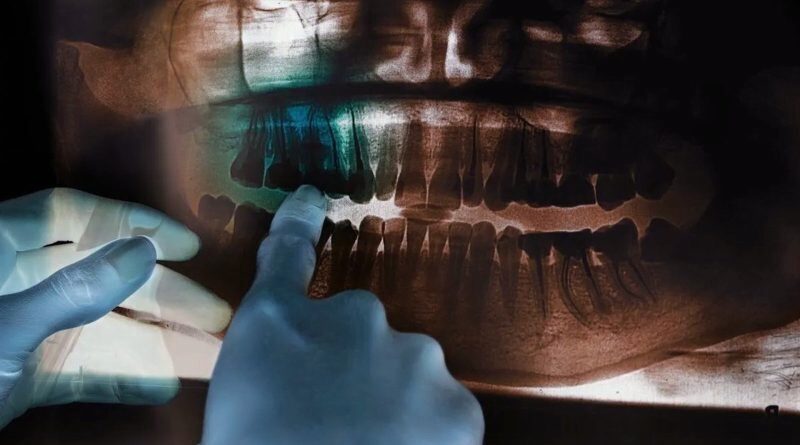

1. Derin Temizlik ve Cerrahi Müdahaleler

- Derin Temizlik: Diş hekimi tarafından tartar ve plakların uzaklaştırılması için yapılan prosedürdür.

- Cerrahi Müdahaleler: Kemik greftleme veya doku yenilenmesi gibi cerrahi işlemler gerekebilir.

Dişlerdeki kemik erimesi nasıl fark edilir?

Diş eti iltihabının kemiklere yayılmasıyla ortaya çıkan periodontitis durumu, diş etinde kanama, kırmızı, mavi veya mor renk değişiklikleri, diş eti çekilmesi, diş etinde büyüme, dişlerin yer değiştirmesi, aralanması, uzaması, sallanması, apse oluşumu, hassasiyet ve kötü ağız kokusu gibi belirtilerle anlaşılabilir.